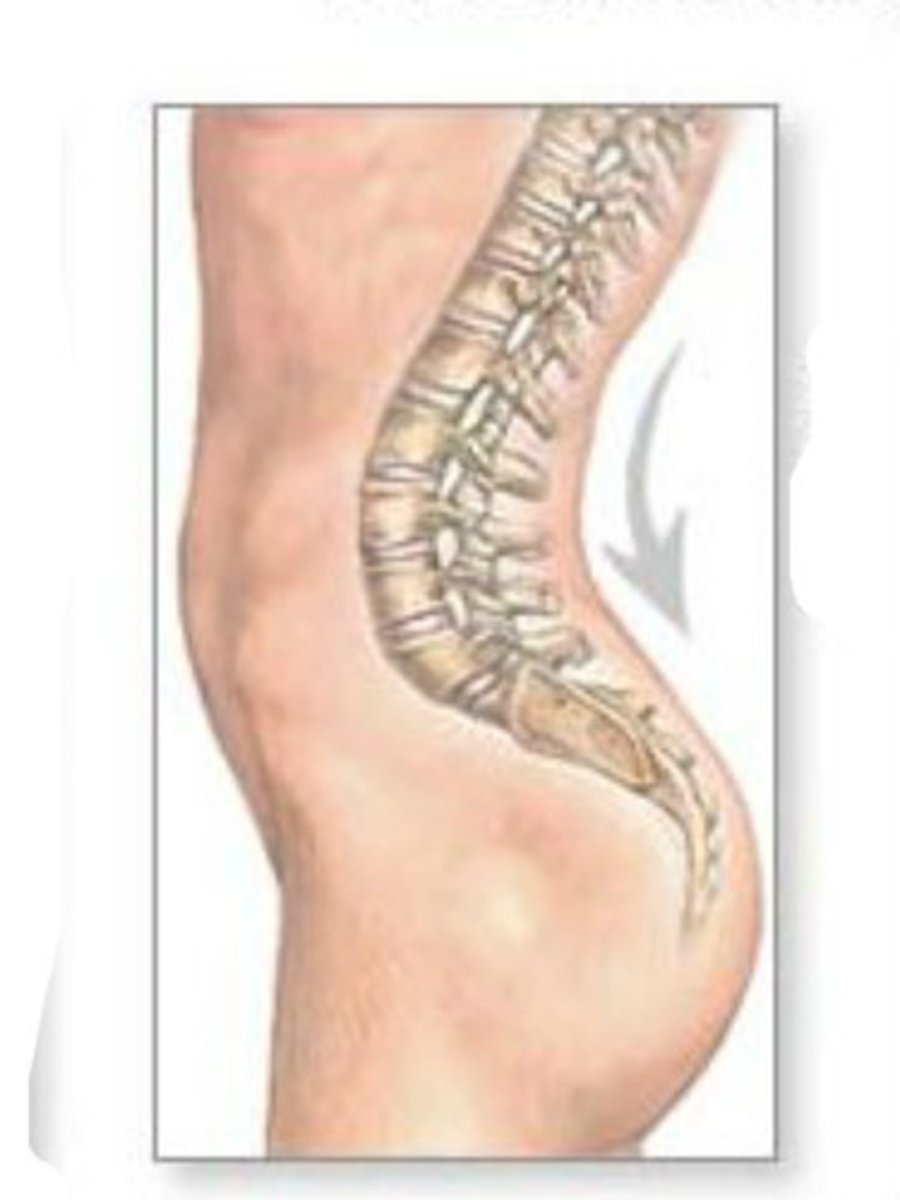

cervial lordosis (convex forwards)

thoracic kyphosis (convex backwards)

lumbar lordosis (convex forwards)

sacral kyphosis (convex backwards)

big blocky vertebra to sustain body weight

what differenciates the L spine vertebra